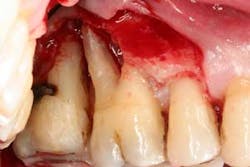

Figure 3: Initial presentation in 2011 of the mandibular anterior sextant, showing advanced hard- and soft-tissue loss.

At presentation, Martin was in his fifties with a medical history significant for controlled hypertension with no known food or drug allergies. He had been lackadaisical with his dental care in the past because of his busy schedule, but he was motivated to get his hygiene and treatment under control. He denied a history of smoking/alcohol/drug use. Based on his full-mouth series (figure 1) and clinical presentation, Martin had generalized, moderate bone loss with localized, severe bone loss in the posterior maxillary right and left quadrants (figures 2a and 2b) as well as the mandibular anterior incisor area (figure 3).